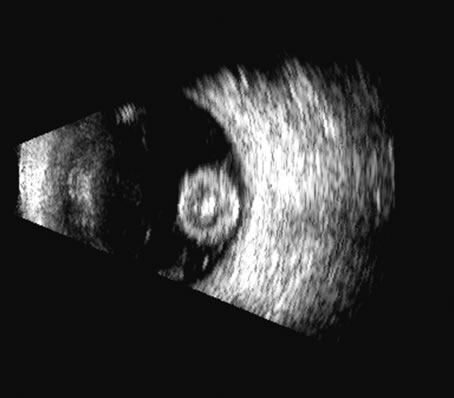

Fig. 17. This patient with a Molteno tube was treated for glaucoma. The top 50 MHz B-scan clearly shows the Molteno Tube (arrow). The bottom 10 MHz B-scan of the same patient demonstrates a choroidal detachment (large arrow) with associated posterior retinal detachment (small arrow). Choroidal elevations are typically convex, highly reflective surfaces with posterior limitation at the vortex vessels. Retina will always attach at the optic nerve. Choroidal elevations are often noted in several quadrants, as seen here.